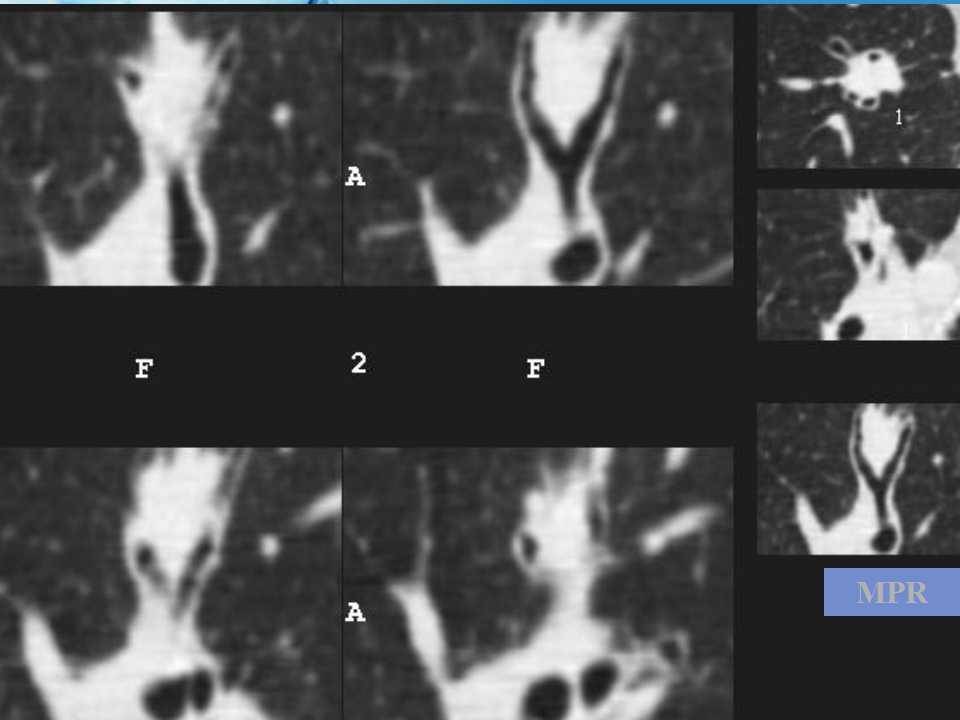

肺癌影像诊断